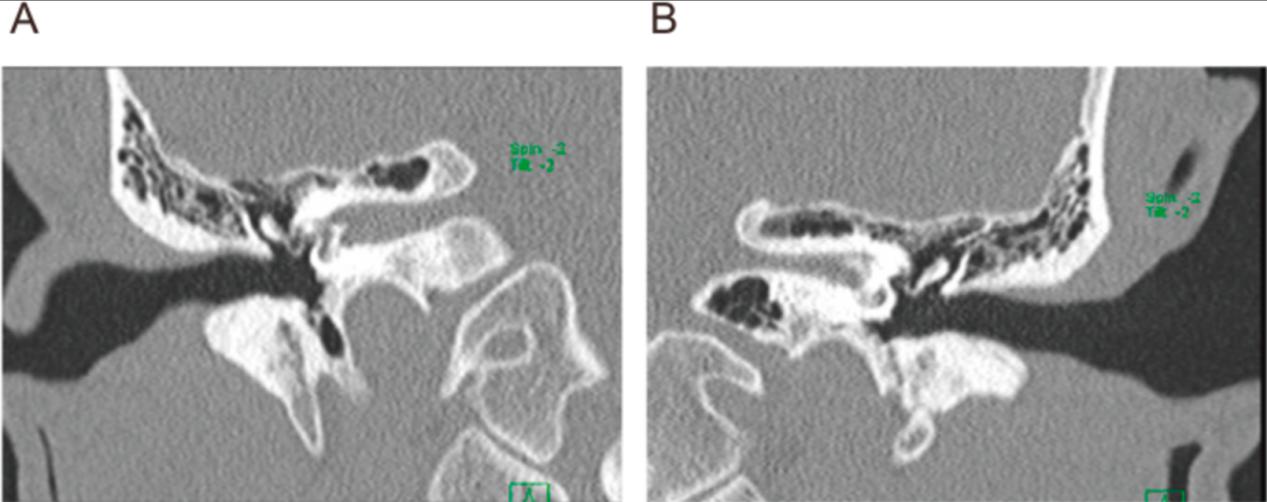

两年后,患者39岁时,因听力迅速恶化,到我院耳鼻咽喉科就诊。听力图显示,与诊断时相比,他的听力明显恶化(图1B)。耳部检查显示鼓膜无红肿,鼓室无积液。计算机断层扫描显示内耳骨结构无改变(图2,A和B)。如前所述,1.5mg地塞米松间歇鼓室给药对患者听力无明显作用。类固醇给药开始后,尽管多次基础和大剂量注射胰岛素类似物,并根据血糖水平调整剂量,但他的血糖明显恶化,并伴有频繁的空腹低血糖。我们开始调查其潜在的全身疾病。尽管白细胞、红细胞、炎症标记物、补体因子和免疫球蛋白的每个亚类都在正常范围内(表1),但他显示抗中性粒细胞胞浆抗体(ANCA)的血清阳性。